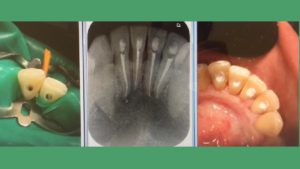

¿Cuándo necesito una endodoncia?

La endodoncia es un procedimiento odontológico que puede diagnosticarse su indicación durante una revisión dental rutinaria. Es comprensible que, en un primer momento, no tengas claro en qué consiste o que te cause cierta aprensión.